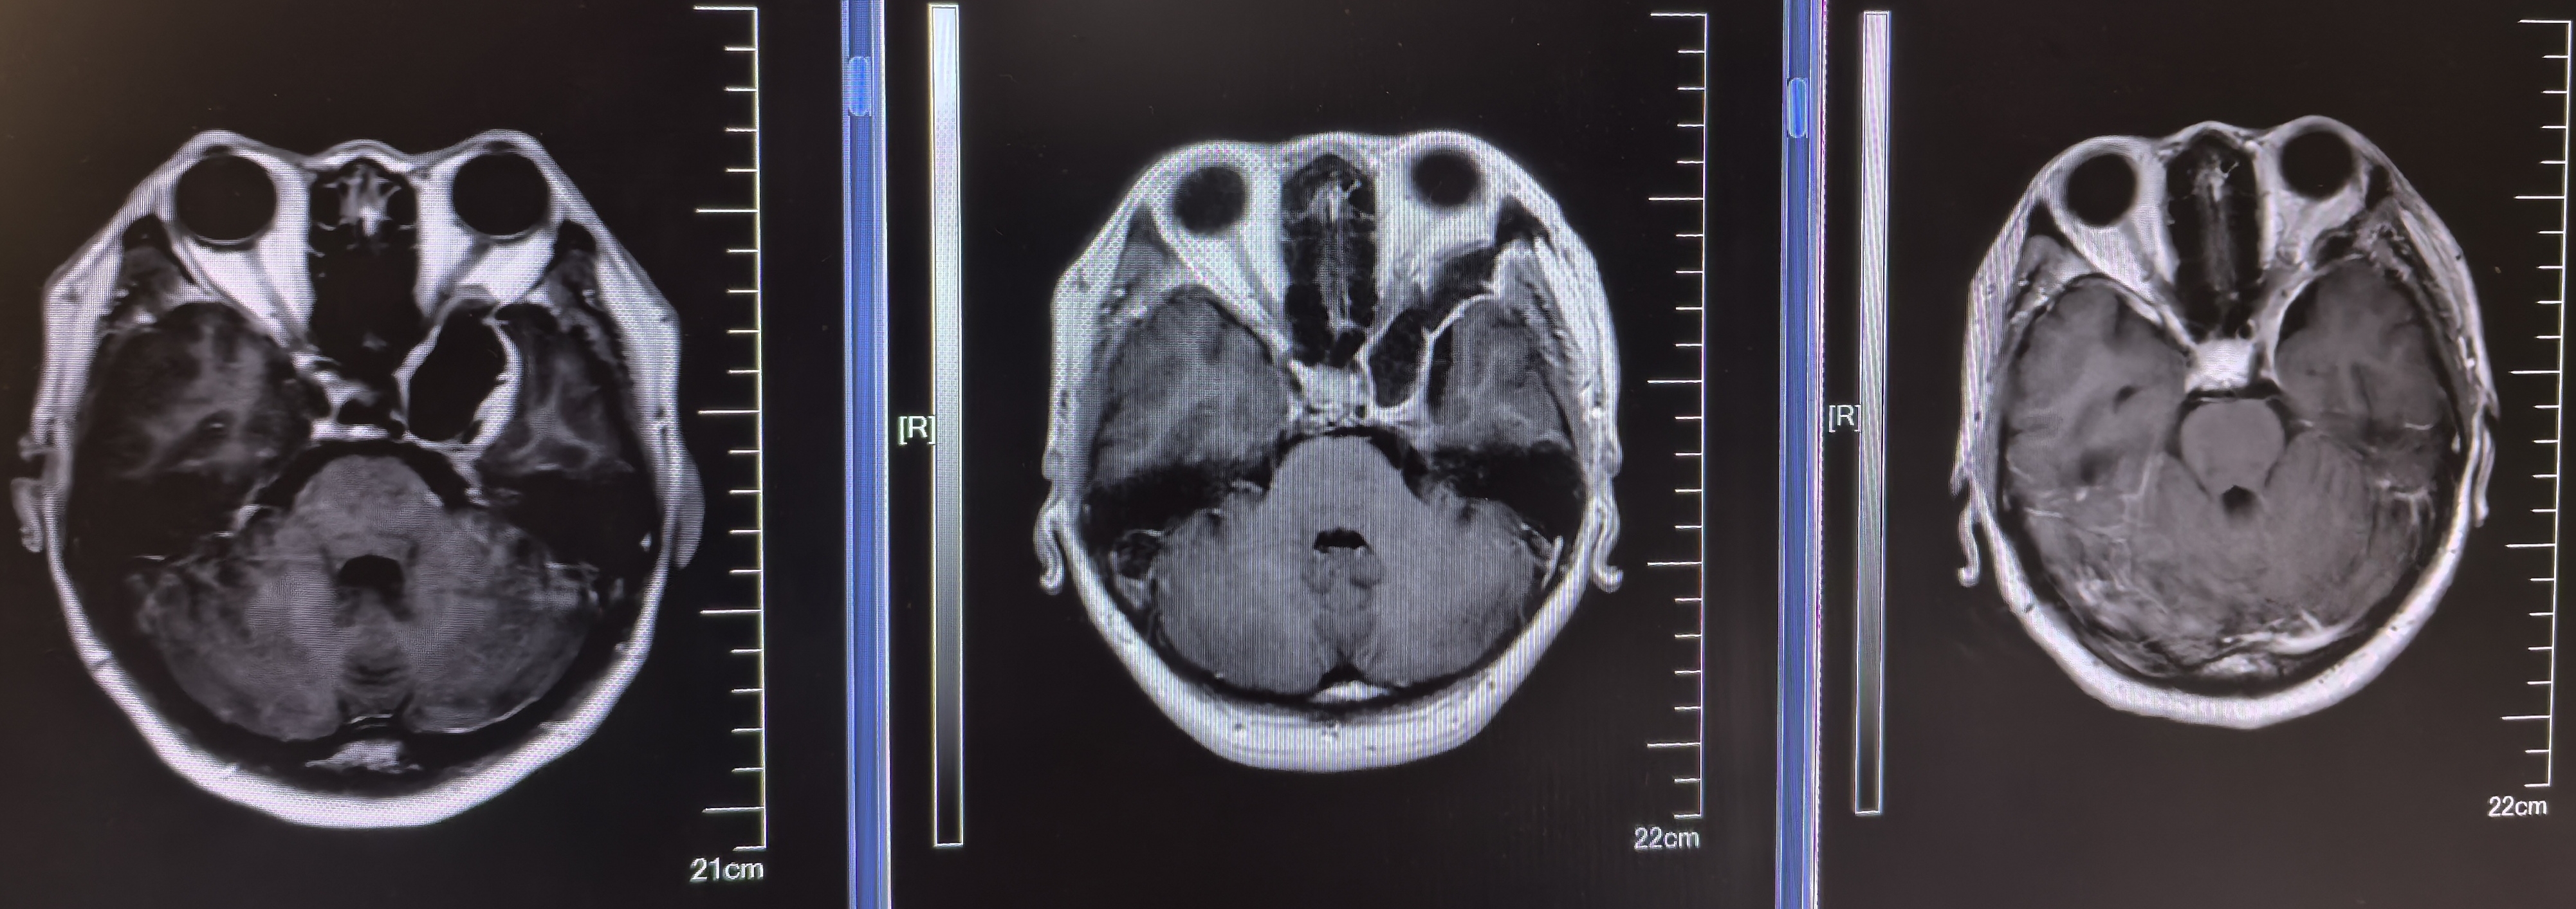

术前磁共振

肿瘤有囊变

术前、术后、术后3个月磁共振对比